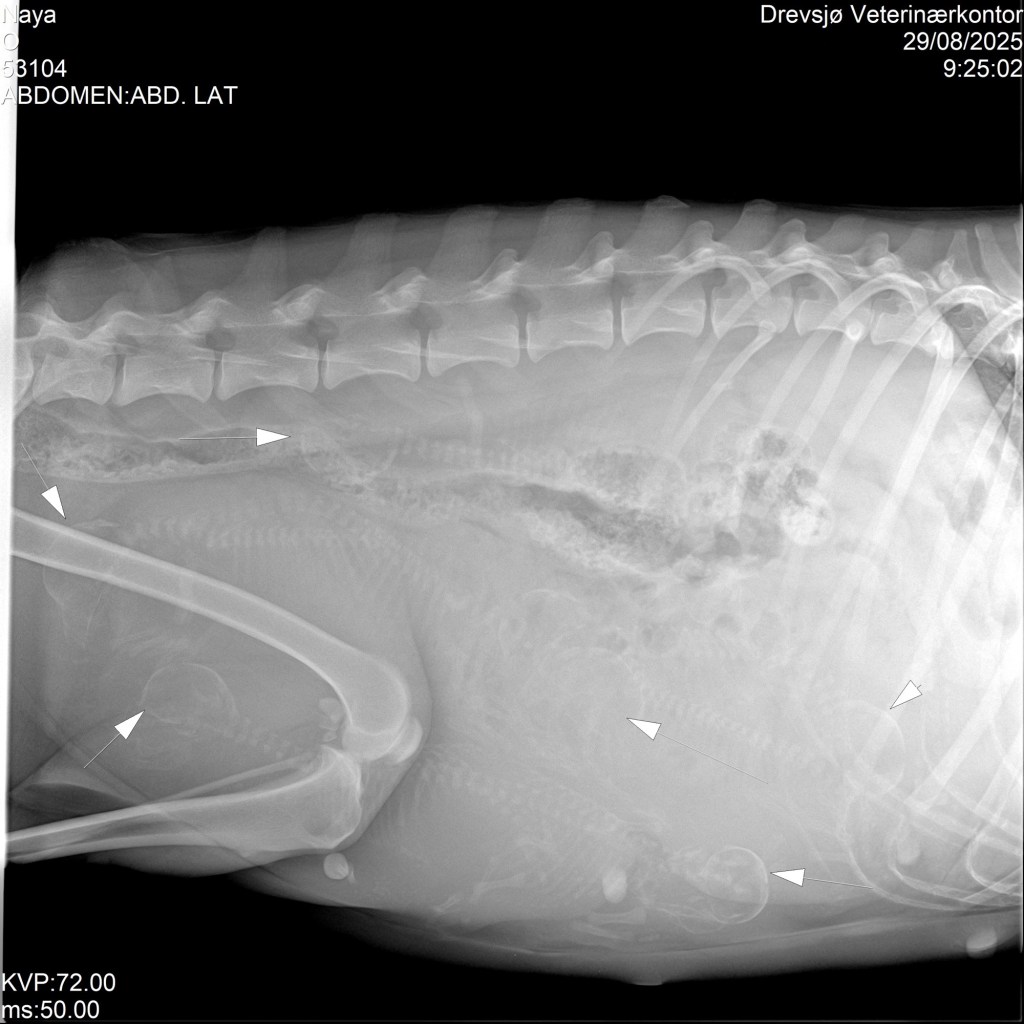

Nå nærmer det seg termin for begge tispene og jeg må si jeg har vært en smule bekymret etter ultralyd og beskjed om et veldig stort kull på Naya. På røntgen er det funnet seks små astronauter hos Naya og en ensom astronaut hos Oliane. Jeg er letter over at Naya får et normalt kull som er akkurat passe stort og litt bekymret for den ene til Oliane. Men vi skal følge henne tett og har kort vei til dyktige fagfolk. Begge har sjekket inn i valpekassene sine og har funnet seg til rette. Naya er tatt ut av trening, mens Oliane har hatt sin siste trening i kveld på en stund ❤️